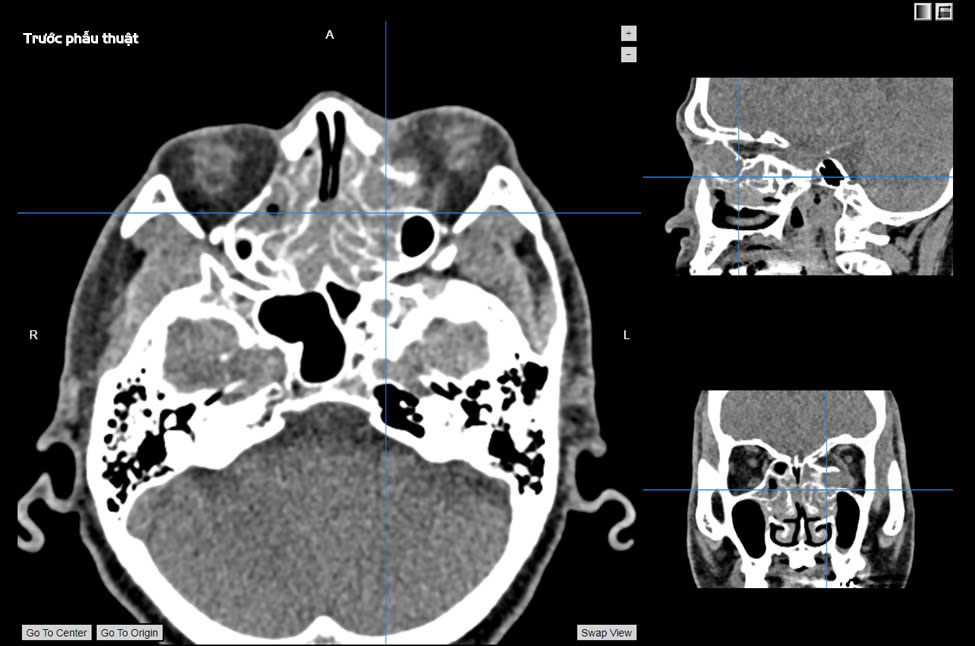

Bệnh nhân xuất hiện triệu chứng sưng đau vùng mắt trái tăng dần 7 ngày trước khi nhập viện tại Khoa Tai Mũi Họng vào ngày 10/03. Qua thăm khám chuyên khoa mắt, các bác sĩ phát hiện tình trạng hạn chế vận động nhãn cầu, mắt lồi và đau khi liếc. Kết quả chụp MRI cho thấy khối u nhầy kích thước 26x24x21mm xuất phát từ xoang sàng trước bên trái, đẩy lồi vào tổ chức phía sau hốc mắt và chèn ép cơ thẳng trong. Bệnh nhân được phẫu thuật ngày 11/03.